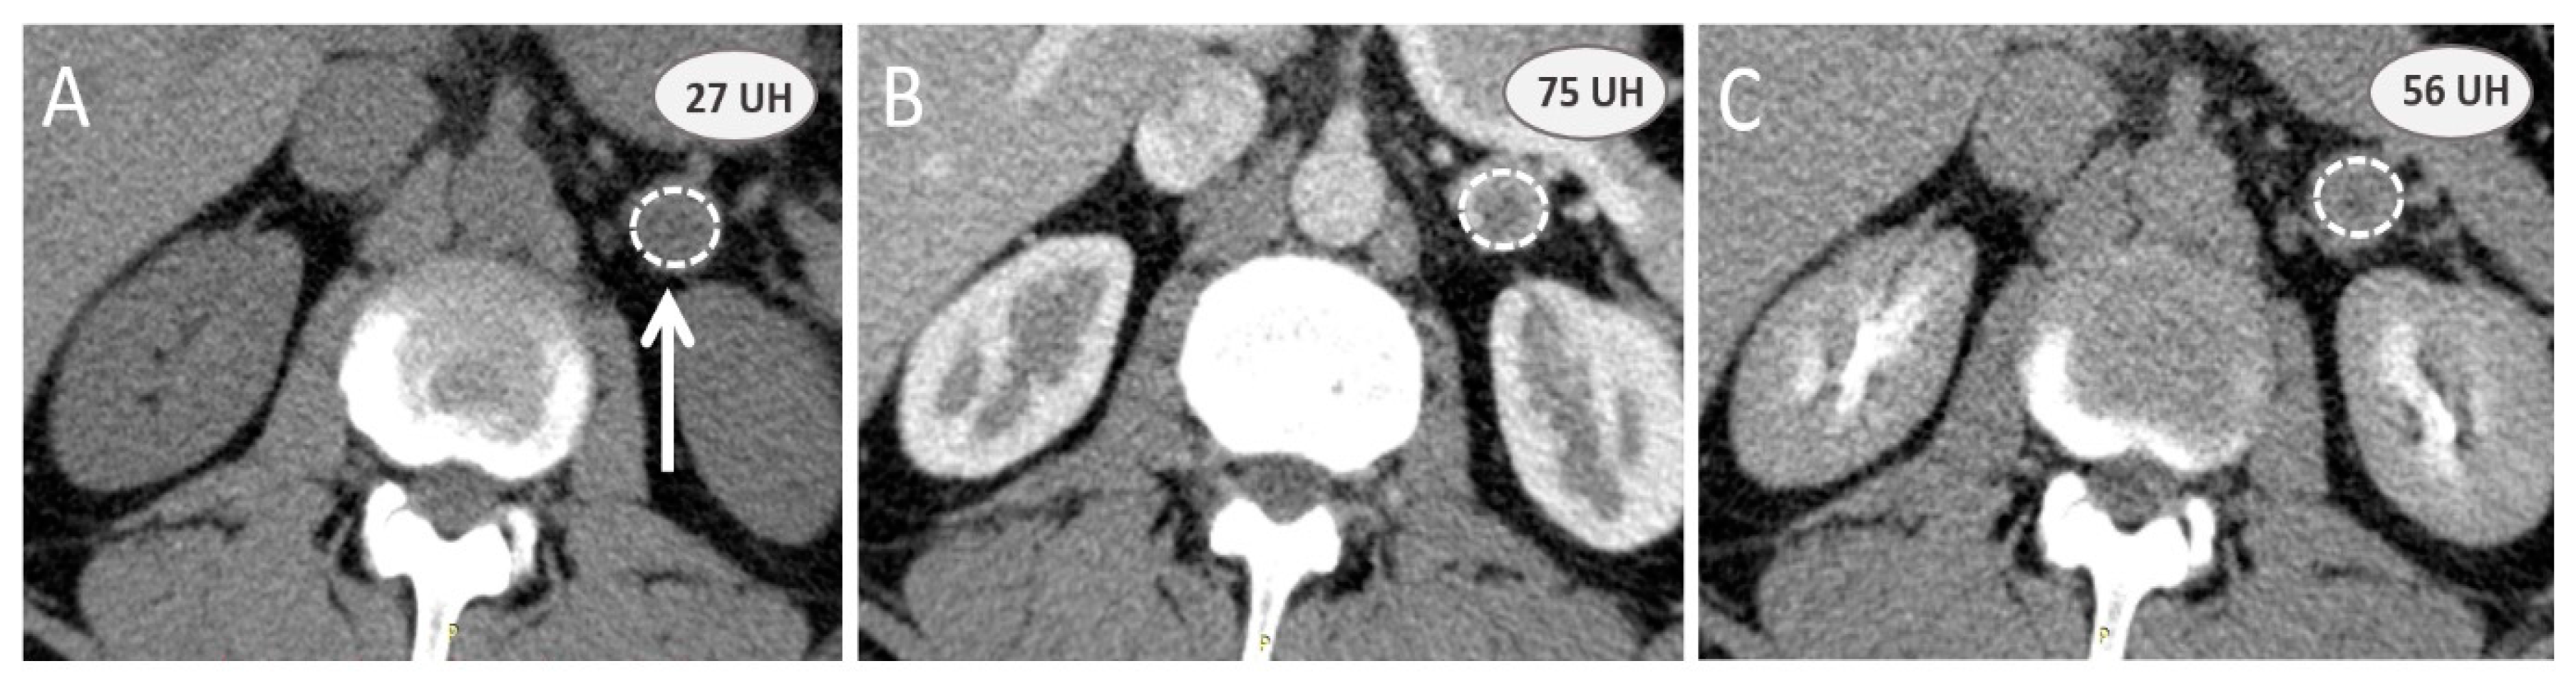

3.1. How to Explore an Indeterminate Adrenal Mass?

3.2. Additional Value of Contrast-Enhanced Computed Tomography Scan